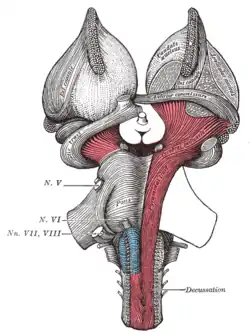

Superficial dissection of brain-stem. Lateral view. Superficial dissection of brain-stem. Ventral view.

Superficial dissection of brain-stem. Ventral view. Dissection of brain-stem. Dorsal view.